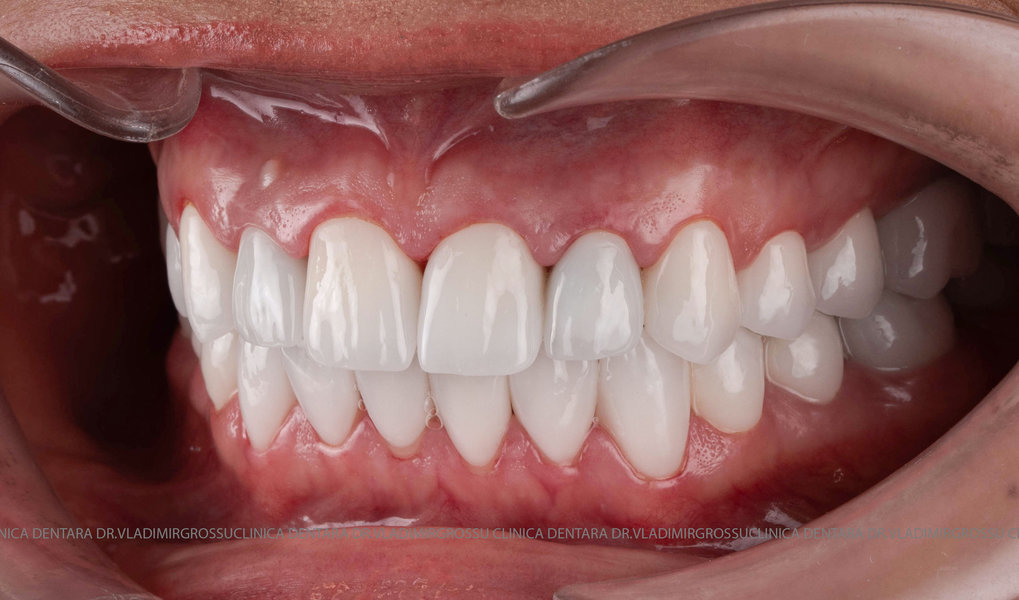

Restaurări cu coroane din zirconiu vs fațete ceramice

Transformările estetice și impactul reabilitării asupra vieții pacienților

Reabilitarea dentară produce o schimbare vizibilă și profundă în aspectul pacientului, cu efecte pozitive evidente asupra stimei de sine și a calității vieții. Mulți pacienți relatează bucuria redobândirii funcției masticatorii și dispariția complexelor legate de aspectul dentar.